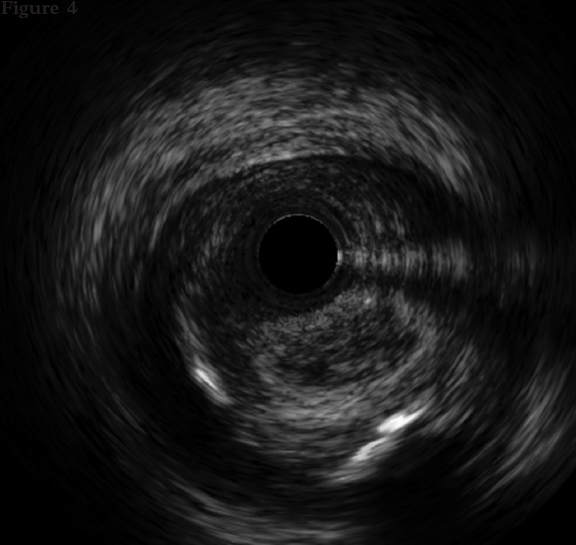

The intravascular ultrasound (IVUS) is useful when the entry site is ambiguous and there are no references to position the guidewire. A lateral branch is required to place the guidewire and IVUS. In these cases, the Slipstream technique38 is very useful. It consists in placing a dual-lumen micro-catheter (DLM) behind the IVUS above the branch guidewire. This increases tremendously the strength exerted with the guidewire that exits the DML lateral port providing better torque and grip (figure 3). The IVUS shows where the occlusion of the vessel is in order to navigate the guidewire (of high-gram, directivity, and torque-response) towards that point (figure 4).

Figure 4. The catheter of intravascular ultrasound in the subintimal space is between the 9 and 12 o’clock positions and true lumen between the 3 and 9 o’clock positions.